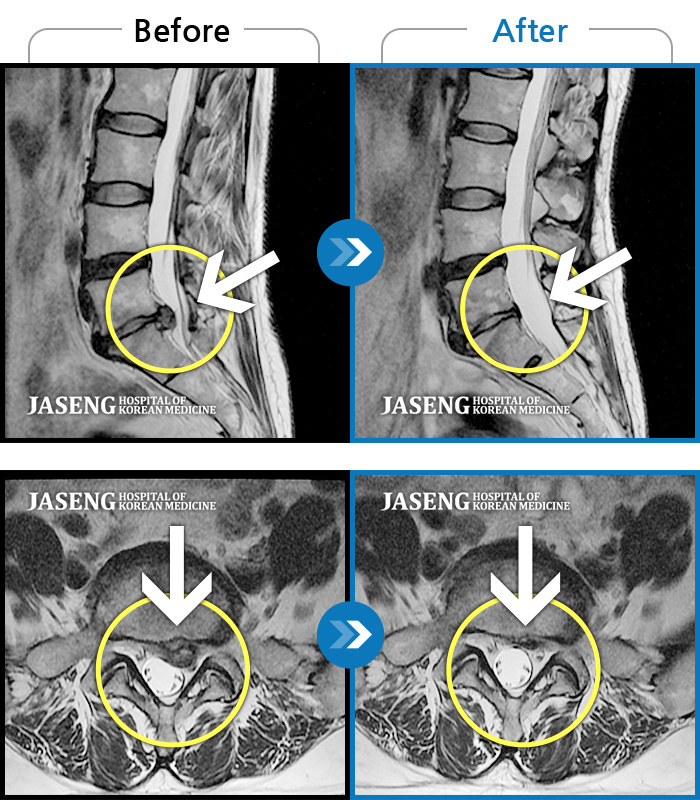

MRI 치료사례

요부 및 좌하지 통증으로 기상 후 통증